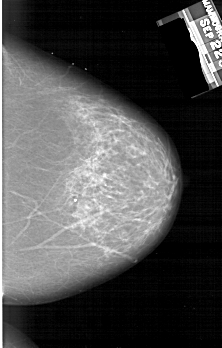

A_1260_1.LEFT_MLO

RIGHT_CC LINES 6256 PIXELS_PER_LINE 3991 BITS_PER_PIXEL 12 RESOLUTION 43.5 NON_OVERLAY